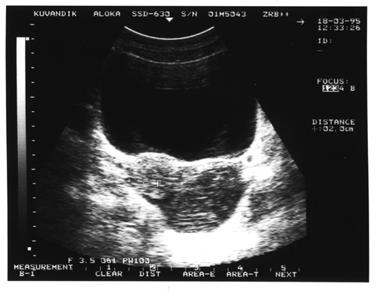

За время работы, врачом ультразвуковой диагностики, в гинекологическом отделении Кувандыкской ЦРБ, с 1994г. по 2000г., мною было осмотрено 417 больных с воспалительными заболеваниями придатков матки. В 21 (5%) случае было диагностировано гнойное тубоовариальное образование, что было подтверждено в дальнейшем при оперативном лечении. В одном случае (из 21) не был диагностирован пиосальпингс и с другой стороны, что привело к незапланированному расширению оперативного вмешательства. Причина диагностической ошибки была в выраженности спаечного процесса в малом тазу и в сложности выведения маточной трубы.

NB! Иллюстрации взяты из книги:

Хачкурузов С.Г. «УЗИ в гинекологии».С-П. 1999г. и собственное наблюдение (рис.3). Вы сможете самостоятельно отредактировать рисунок в любом графическом редакторе, чтобы изменить к примеру, дату исследования либо название стационара, ФИО больного. Либо можете полностью удалить графику.